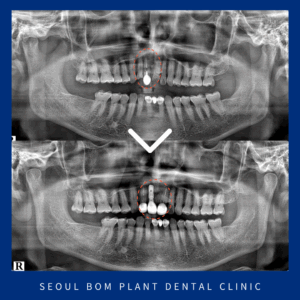

오륜동치과 상악동 거상술을 동반하여

오륜동치과 상악동 거상술을 동반하여 안녕하세요. 서울봄플란트치과 대표원장 송원섭입니다. ​ 치아는 이동하려고 하는 성질이 있어 치아를 상실하게 된다면 빈 공간으로 치열이 이동하면서 전체적으로 비정상적인 위치를 가지게 되는데요. ​ 이렇게 되면 제대로 된 교합을 만들 수 없게 되어 구강 내 많은 문제가 더보기…